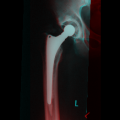

b. Medical application: Hip prosthesis registration

Hip replacement is a surgical procedure in which the hip joint is replaced by a prosthetic implant. Such joint replacement surgery generally is conducted to relieve arthritis pain or fix severe physical joint damage. In the short term post-operatively, infection is a major concern. Deep infection will often require one or two stage revision surgery. Recurrent dislocation is another indication for revision. In the long term, many problems relate to osteolysis from wear debris. An inflammatory process causes bone resorption and subsequent loosening or fracture often requiring revision surgery.

The following figure shows a result of our method. The red channel of the first image represents the template. By applying the inverse of the recovered transformation to the observation, we get a registered image shown in the green channel. The contour overlay image shows the contour of the registered observation object in yellow color over the template image.

| Registration of hip prosthesis X-ray images. Each image pair has been taken over a period of time about the same patient. The overlayed contour in the second row shows the aligned contour of the corresponding image in the first row. For each pair, we have also evaluated the measure. | ||||